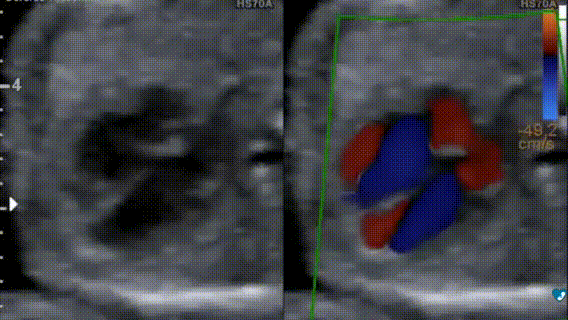

Ecocardiografia fetale - 17 settimane